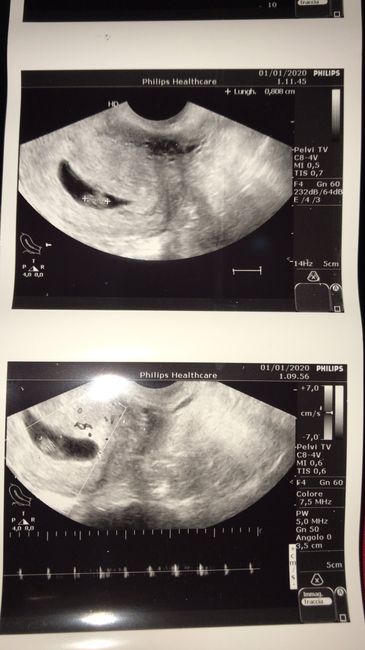

Questa è la mia eco a 7+4, eco interna... Chi ne capisce del metodo ramzi? 🤔